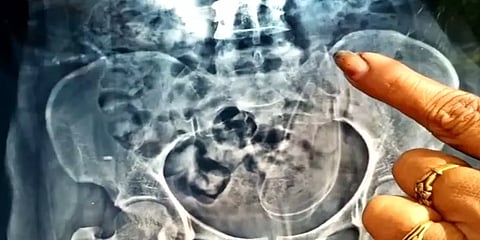

இதனையடுத்து சில நாட்களுக்கு முன்பு கள்ளக்குறிச்சியில் உள்ள தனது உறவினர் வீட்டுக்குச் சென்றபோது மீண்டும் வயிற்று வலி ஏற்பட்டுள்ளது. உடனே அங்குள்ள தனியார் மருத்துவமனையில் கலைச்செல்வி அனுமதிக்கப்பட்டார். அங்கு மருத்துவர்கள் அவரின் வயிற்றுப் பகுதியில் ஸ்கேன் செய்து பார்த்தனர்.

அப்போது ஏற்கெனவே அறுவை சிகிச்சை செய்த வயிற்றுப் பகுதியில் அறுவை சிகிச்சை பயன்படுத்தப்படும் பொருள் ஒன்று இருப்பதாக அறிக்கையில் தெரிவிக்கப்பட்டது. இதனால் அதிர்ச்சி அடைந்த கலைச்செல்வி தனக்கு அறுவை சிகிச்சை செய்த காட்டுமன்னார்கோவில் தனியார் மருத்துவமனையில் முறையிட்டுள்ளார்.